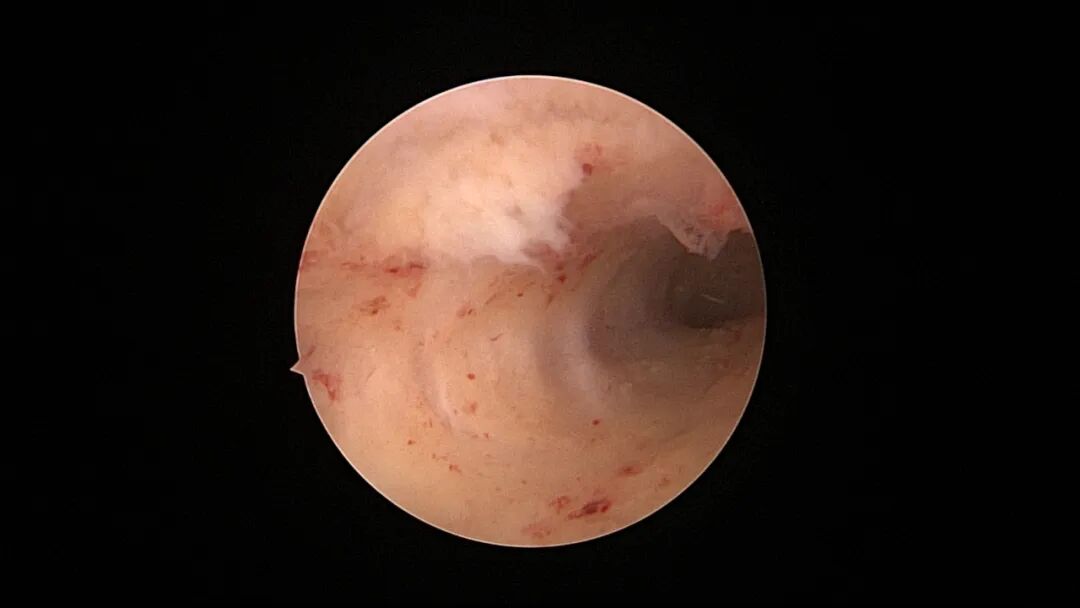

病例3:30岁,G8P1,顺产1次。月经淋漓不净10余天,月经周期第11天B超示宫腔回声宽约0.5cm,内可见絮状回声,有流动感。宫腔镜探查,宫颈管见血迹,宫腔粘连,内膜草莓状,单极电针分粘,内膜活检,病检为增殖期样子宫内膜伴出血。

| ||||